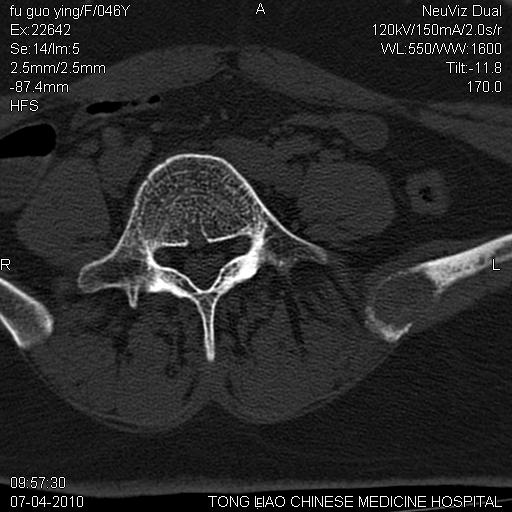

标题: CT27489:患者腰疼,其余椎体未见异常! [打印本页]

标题: CT27489:患者腰疼,其余椎体未见异常!

髂骨考虑转移瘤 椎体病变不像转移瘤

女性46岁,左髂骨溶骨性破坏+软组织肿块,考虑转移瘤,腰椎为退变/增生硬化/软骨下骨囊变。